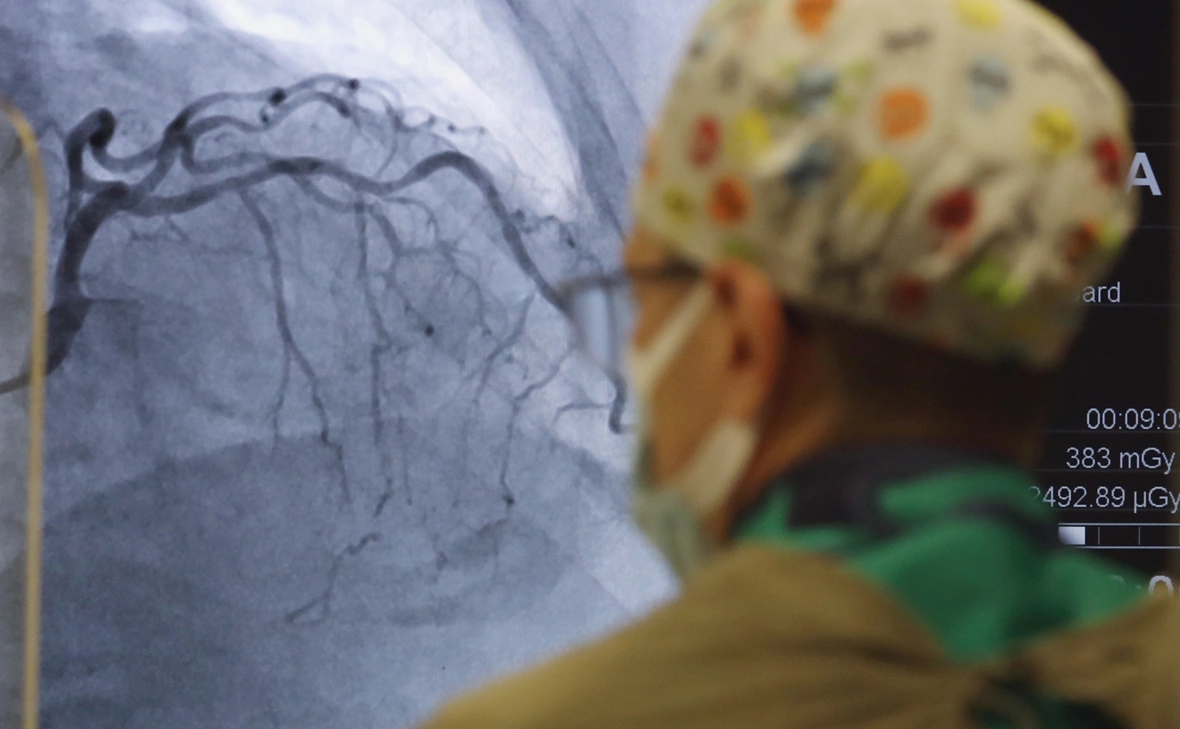

Фото: Михаил Терещенко / ТАСС